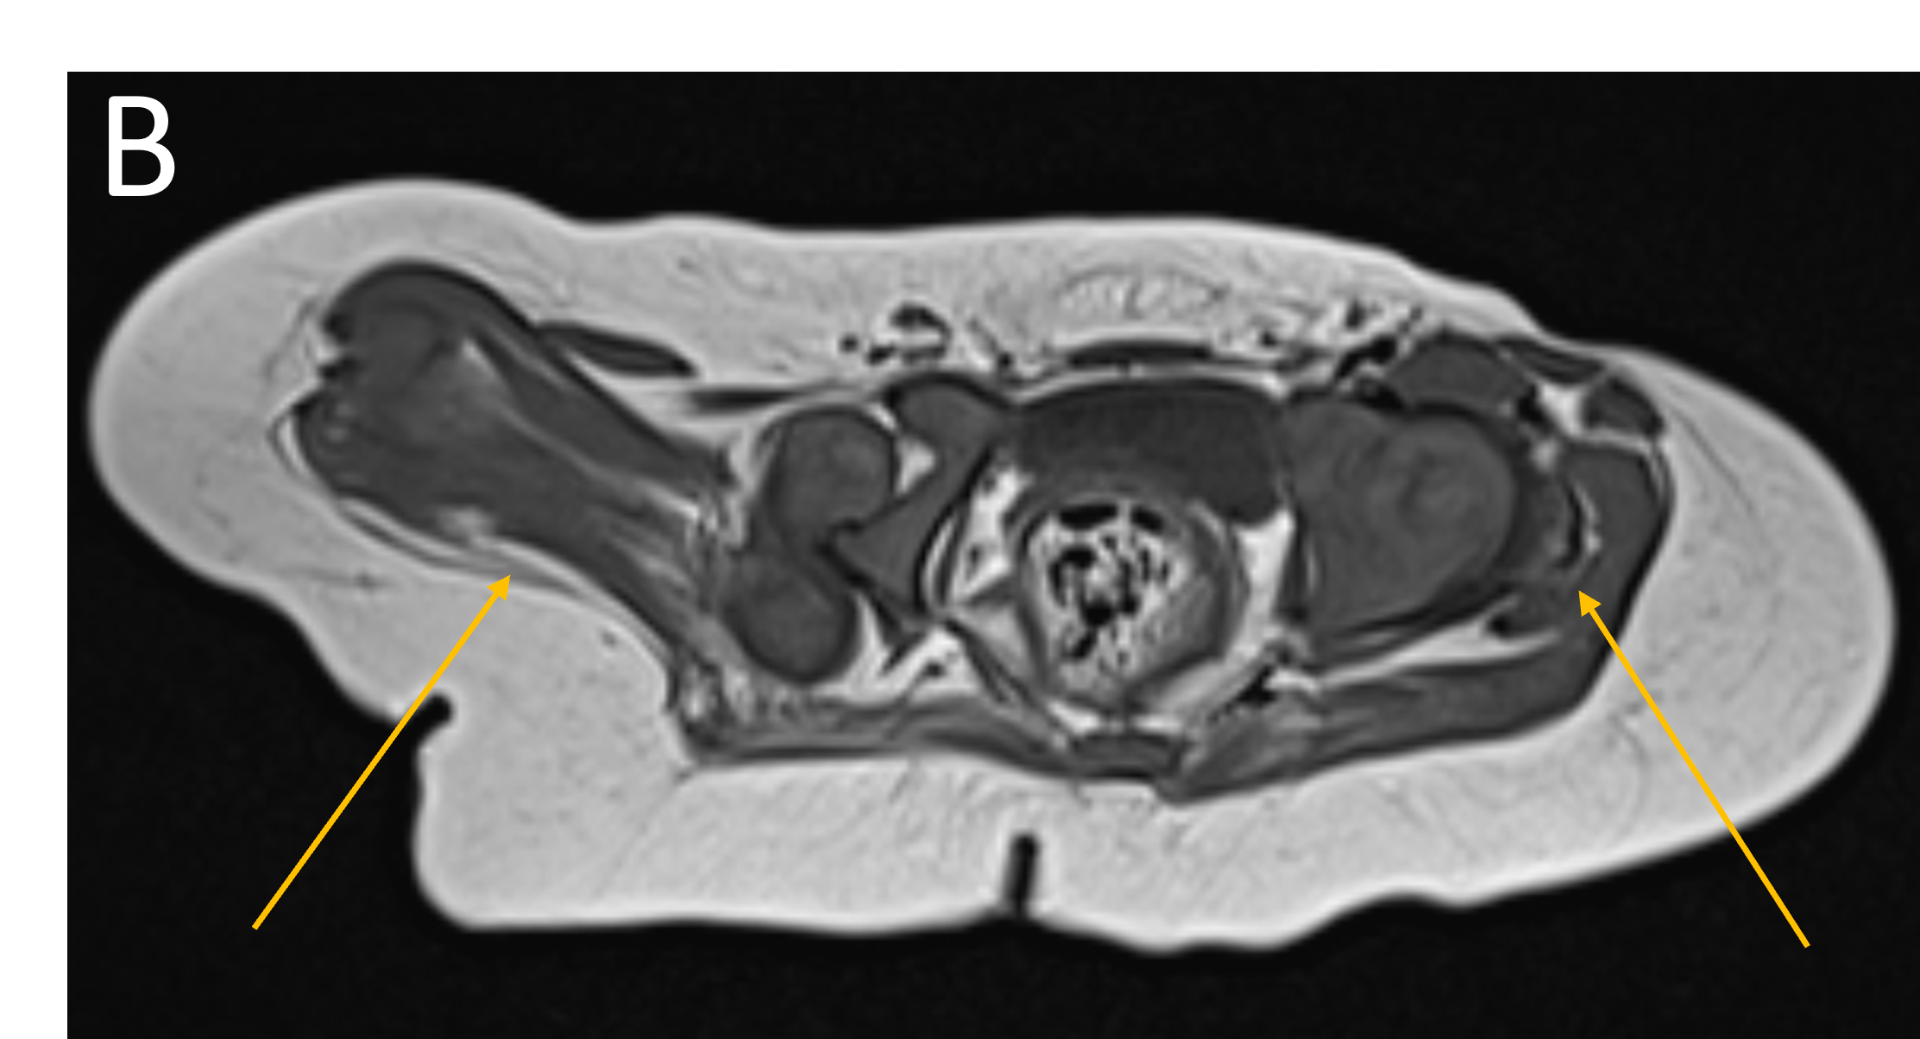

- B.FINDINGS – MR BILATERAL HIPS

- B.LEGENDS – MR BILATERAL HIPS : Generalised atrophy of muscles of thigh and gluteal region on the right compared to the left.